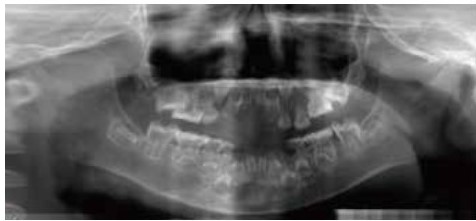

7歳0か月時のパノラマエックス線画像では、萌出歯の形成不全を認め、永久歯胚の形成状態もよくない。